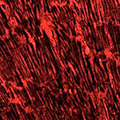

Herzzellen, die ein rot fluoreszierendes Antagomir aufgenommen haben

Unter einem konfokalen Lasermikroskop zeigt die kräftige rote Färbung der untersuchten Herzzellen, dass sie das mit einem roten Fluoreszenzfarbstoff markierte Antagomir aufgenommen haben